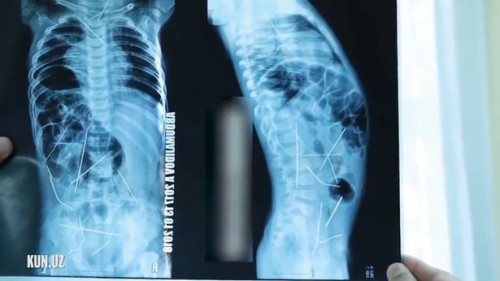

Bé trai 11 tháng tuổi ở Ferghana, Uzbekista sốt cao, tiểu tiện khó được đưa vào viện cấp cứu. Khi chụp X-quang, các bác sĩ không thể ngờ vào mắt mình khi phát hiện trong bụng bệnh nhi có tới 16 cây kim khâu.

Theo thông tin trên trang Mirror, các bác sĩ của một bệnh viện ở vùng Ferghana, Uzbekistan đã phẫu thuật thành công lấy ra 13/16 cây kim khâu trong bụng bé trai 11 tháng tuổi

Sau khi chụp X-quang, các bác sĩ phát hiện trong bụng bệnh nhi có 16 cây kim khâu.

Theo đó, bé trai được mẹ đưa tới bệnh viện trong tình trạng sốt cao và gặp khó khăn trong việc tiểu tiện. Sau khi chụp X-quang, các bác sĩ phát hiện trong bụng bệnh nhi có 16 cây kim khâu.

Em bé sau đó được chuyển vào phòng phẫu thuật trung tâm cấp cứu ở thành phố Tashkent, và được tiến hành ca mổ cấp cứu gấp trong suốt 9 tiếng. Tuy nhiên, ca phẫu thuật lần này các bác sĩ mới chỉ lấy ra 13 cây kim, bao gồm ba cây kim ở ngực, 9 cây ở bụng và một cây ở cổ. Cậu bé 11 tháng tuổi sẽ phải trải qua ca phẫu thuật thứ 2 để lấy nốt 3 cây kim khâu còn lại ra ngoài.

Gia đình bệnh nhi cho hay, họ hoàn toàn không biết gì về chuyện này cho đến khi cậu bé có những triệu chứng trên. Còn các bác sĩ lại cho rằng đã có ai đó cố ý chọc những cây kim trên vào cơ thể đứa bé vì em không thể tự nuốt chúng vào người. Các bác sĩ cũng chẩn đoán những cây kim đó đã ở trong cơ thể cậu bé ít nhất là 1 tháng.

Ban đầu, các bác sĩ nghi ngờ bé bị viêm phổi, tuy nhiên, kết quả X-quang cho thấy những chiếc kim đang mắc kẹt trong tim, cổ, cột sống và bàng quang em.